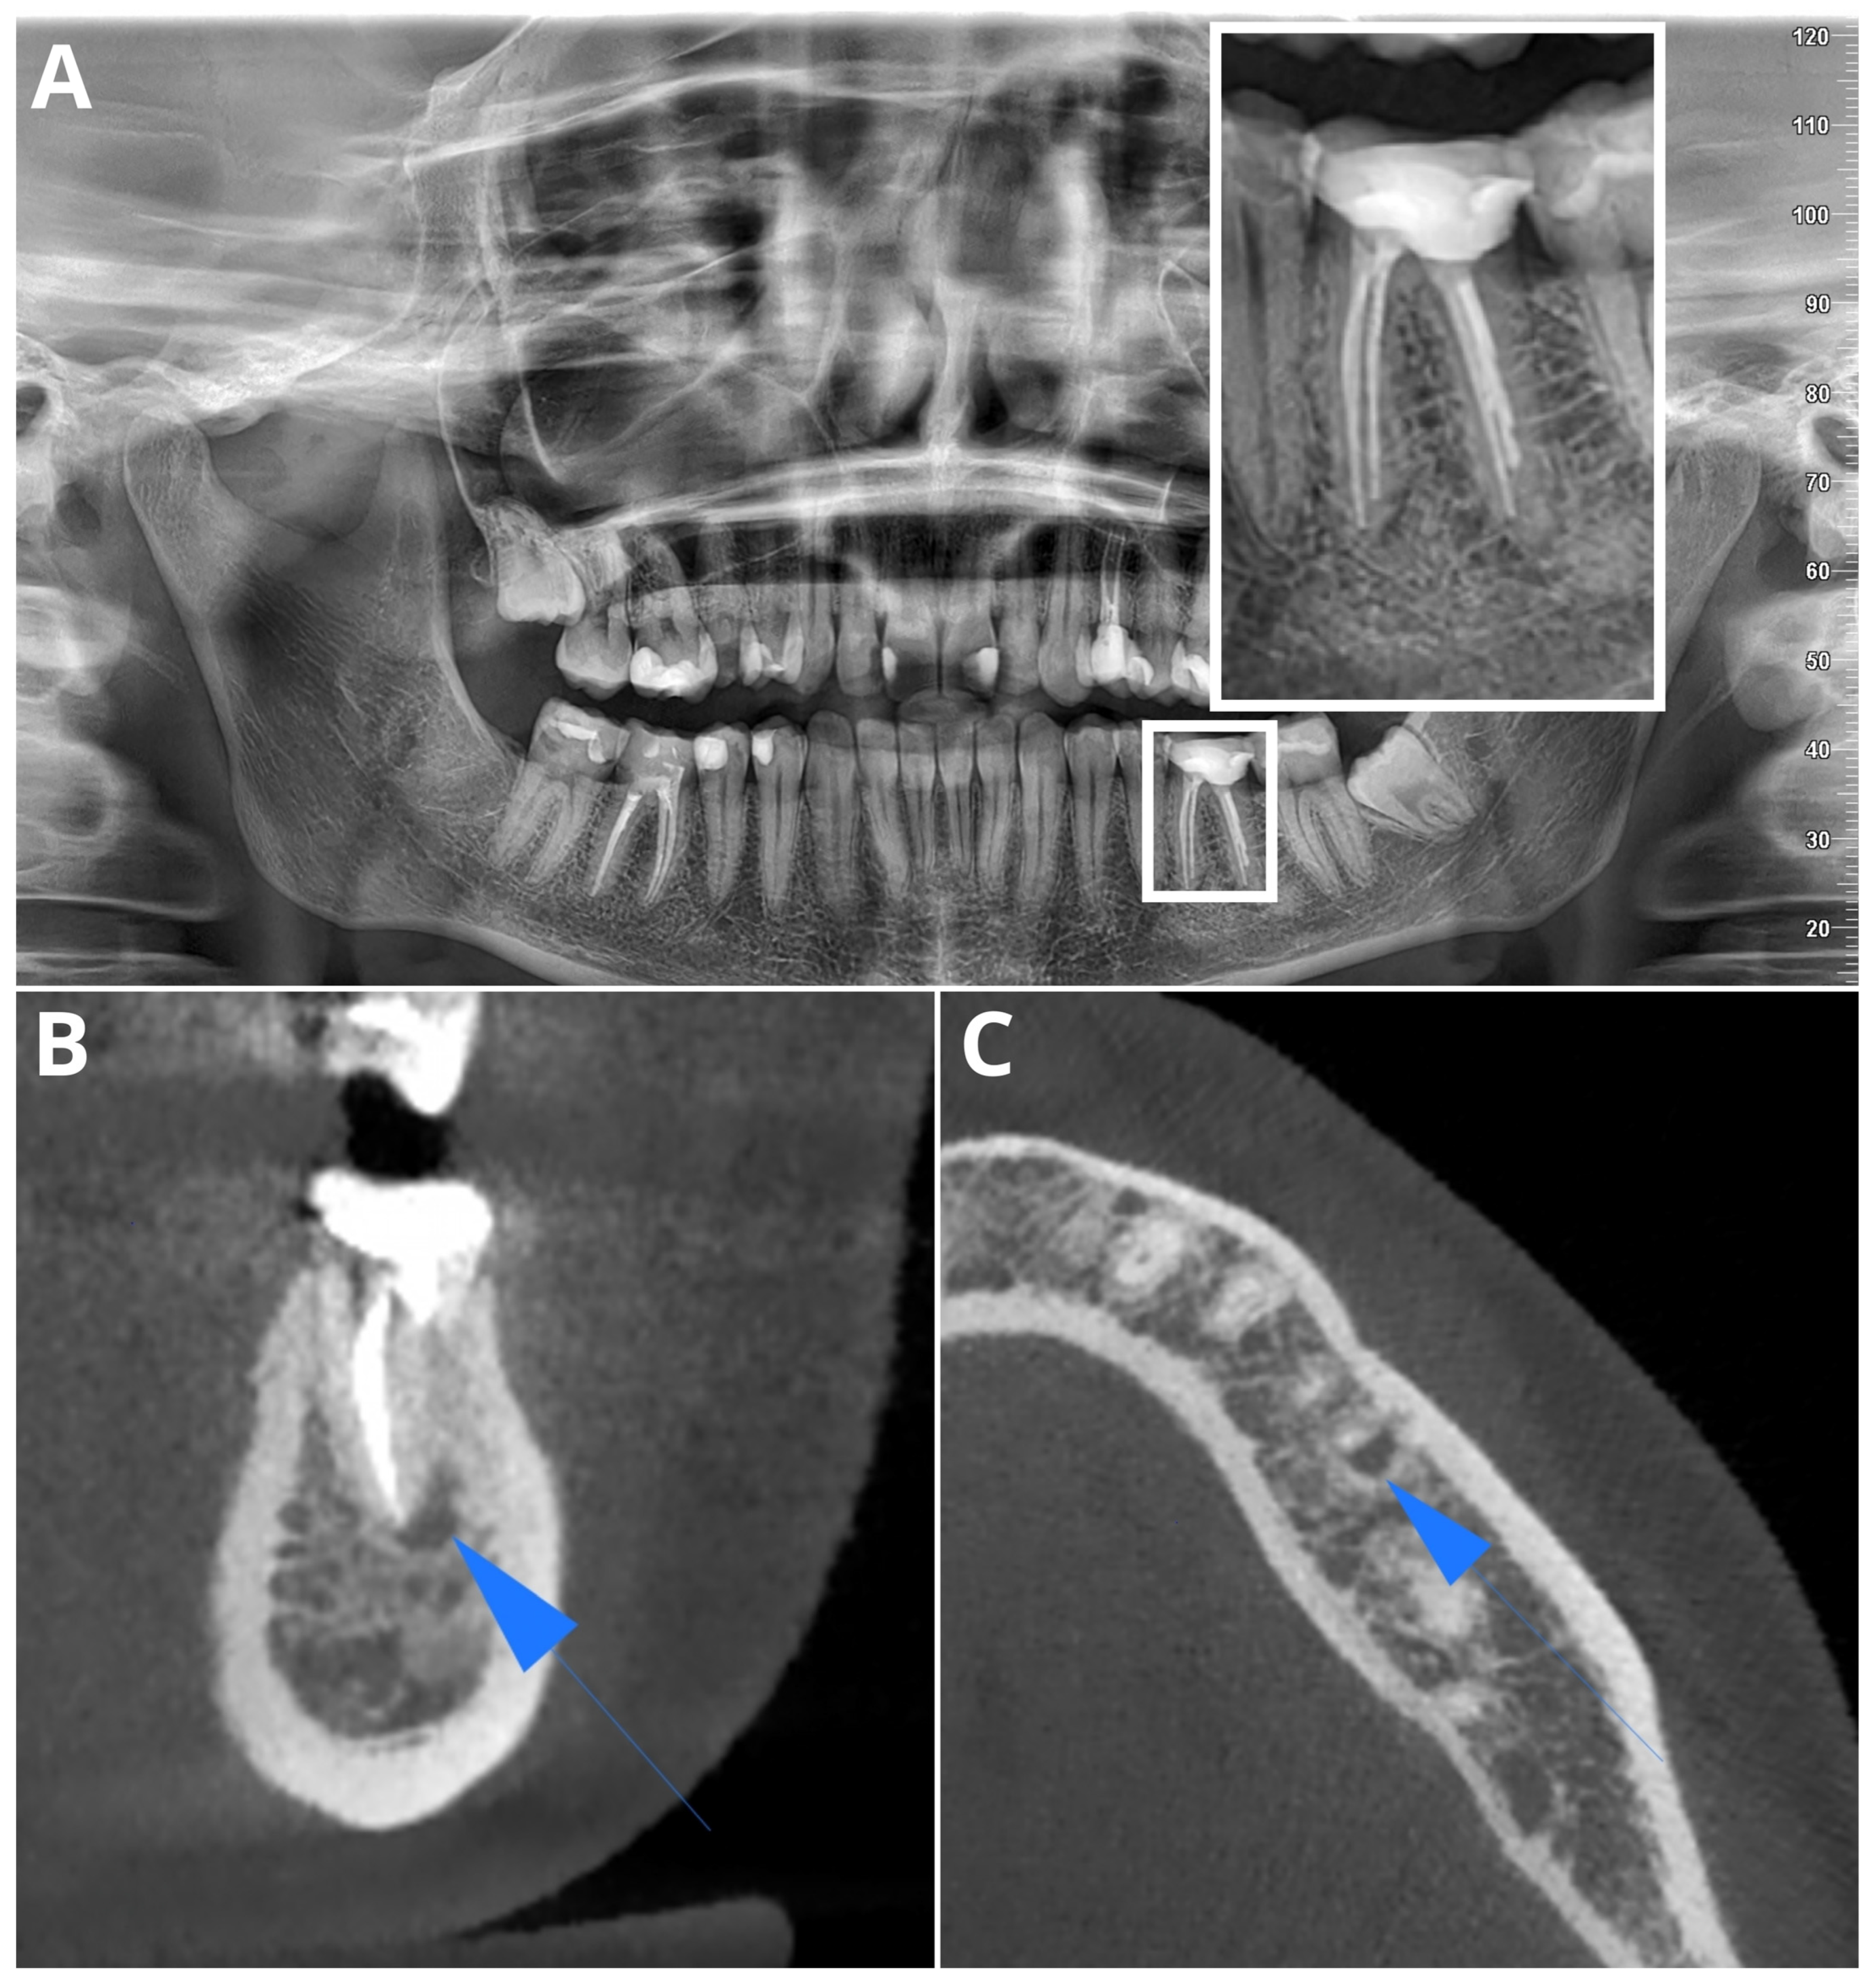

2. Materials and Methods

2.2. Image Acquisition and Post-Processing

2.3. Multireader Evaluation

2.4. AI Evaluation